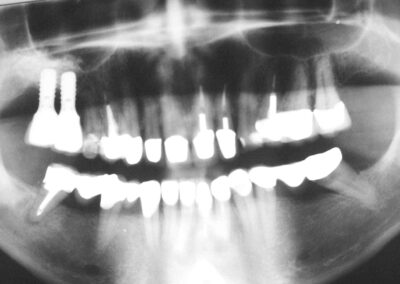

5 Jahre nach Implantation und prothetischer Versorgung im OK. Bei 16 und 27 jeweils mit internem Sinuslift mit Cerasorb. Die Straumann-Implantate (regular neck) sind jeweils komplett, also auch mit ihrem polierten Anteil im Knochen versenkt. Das Implantat regio 23/24 wurde aufgrund eines umfangreichen Defektes in regio 23 absichtlich schräg inseriert. Der Knochenverlauf ist gegenüber der Kontrollaufnahme nach Implantation praktisch unverändert.

- Wir denken nach wie vor, dass das wesentliche Problem der Entstehung einer Periimplantitis in freiliegenden rauen Anteilen des Implantats begründet ist, auch wenn die Entwicklung im Implantatdesign nachgerade in die gegensätzliche Richtung zu gehen scheint. Deshalb präparieren wir den Implantat-Stollen beispielsweise 12mm lang, inserieren aber nur ein 10 mm langes Implantat, das wir dafür jedoch vollständig versenken, also auch seinen polierten Anteil. Bei 10 mm Knochenangebot, inserieren wir analog ein 8mm-Implantat. Irgendwo meinen wir auch einmal eine Studie mit der Aussage gelesen zu haben, dass die Periimplantitis bei vollständig polierten Implantaten weniger häufig auftritt als bei rauen. Wir denken, dass wir durch unser Vorgehen die jeweiligen Vorteile von rauen und glatten Implantaten ideal kombinieren. Zumindest wird so ein nie auszuschließender, leichter Knochenabbau unmittelbar im Anschluss an die Implantation in keinem Falle zum Freiliegen rauer Implantatanteile führen.